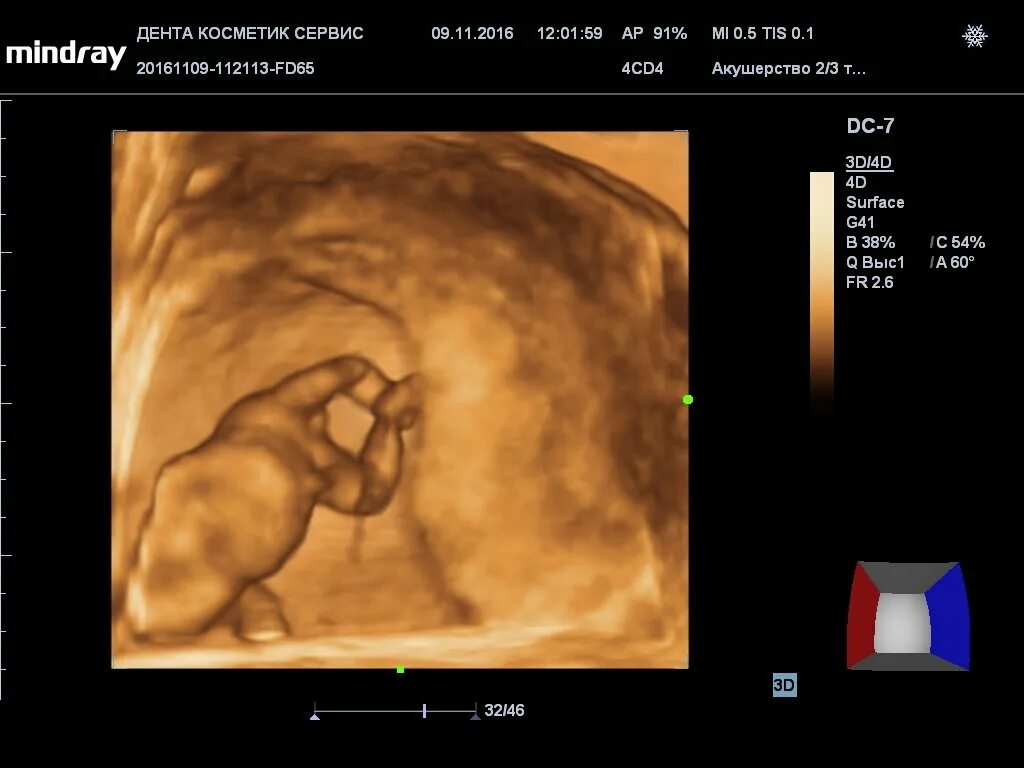

Может врач ошибиться с полом ребенка